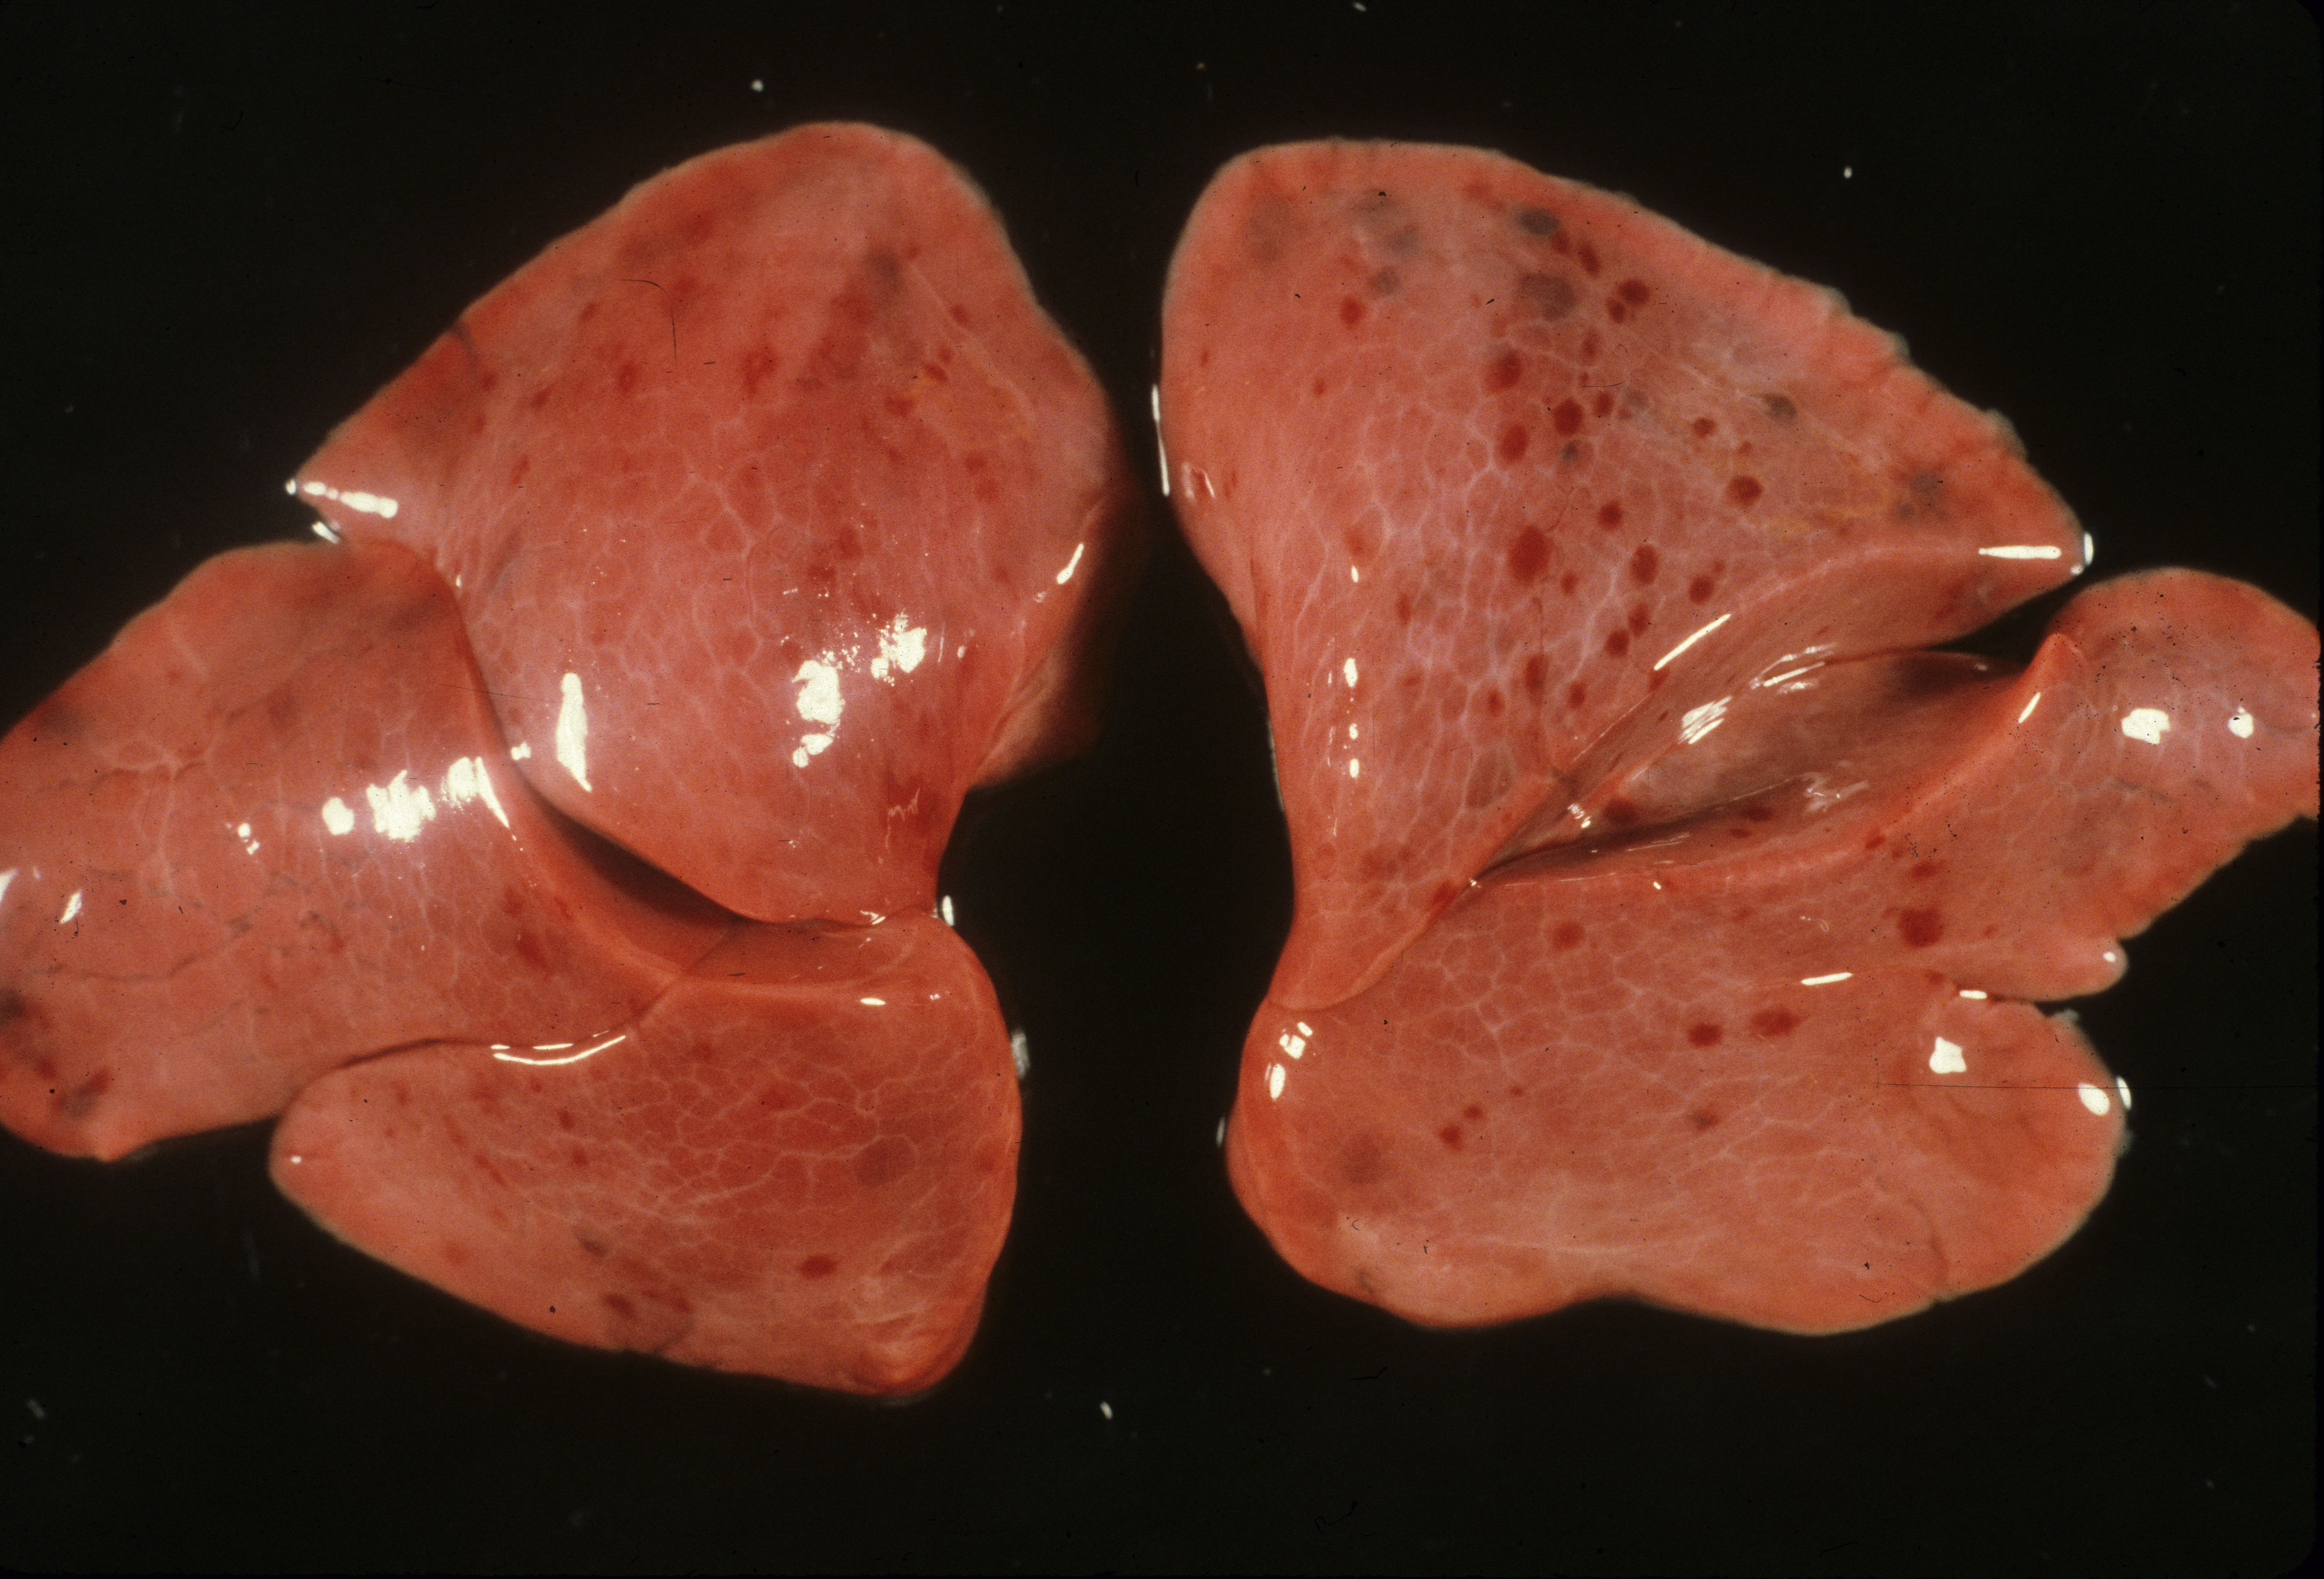

Color: The normal lung is pink. In the stillborn infant, it may be red from hemoglobin staining from autolysis or from vascular congestion, or rarely pneumonitis. Petechiae of the visceral pleura may be present. The significance of the petechiae is discussed in the section on thymus. If the fetus is anemic, the lungs will be paler than normal. With bacterial overgrowth there may be visible foci of gaseous expansion on the surface. Foci of pneumonitis or deep hemorrhage may be seen on the surface.

Pulmonary hypoplasia: Pulmonary hypoplasia may be apparent on opening the chest because the small lungs are obscured by the heart (Fig 1a,b).

The lung lobules should be identified noting three on the right and two lobes with a lingua on the left (Fig 2).